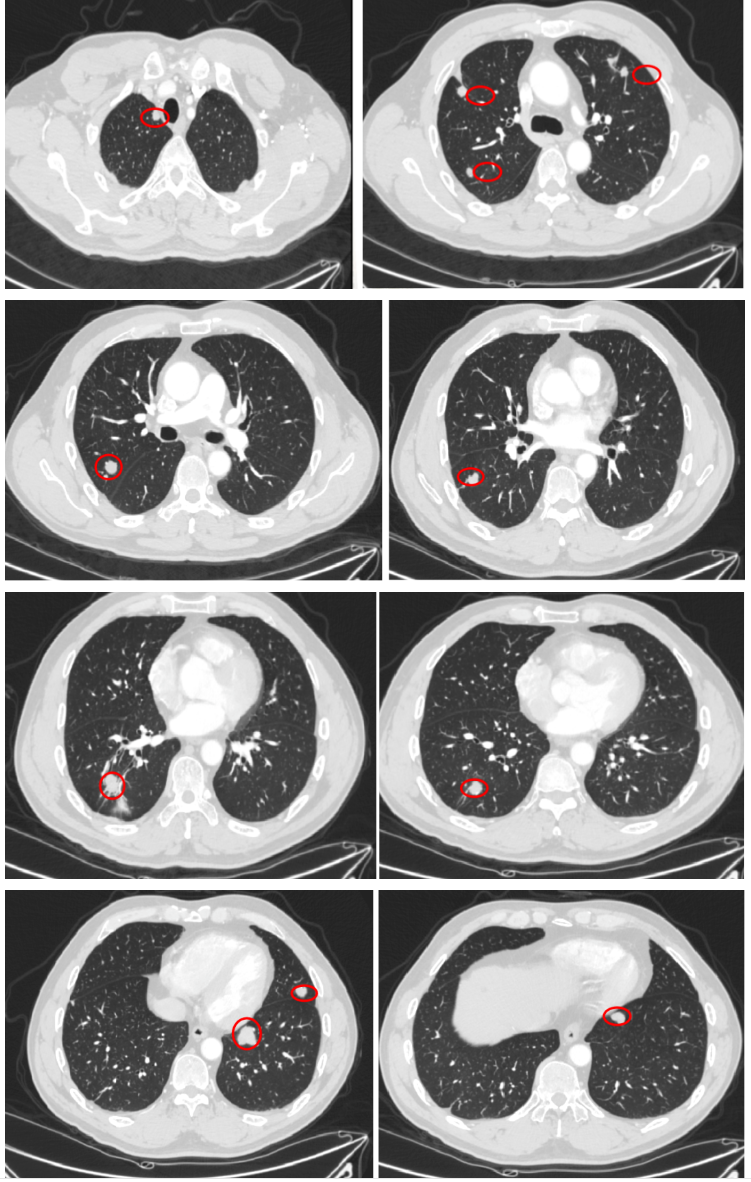

2018-10-11 胸部CT:双肺转移瘤较前进展。

2019-4至2019-6 外院行肺内转移瘤(6处)射频消融治疗。

2020-1-7强化CT(我院)

入院诊断:直肠(上段)中分化腺癌;cT0N0M1,IV期;双肺转移;MSS型,RAS/BRAF基因野生型;ERBB2基因扩增型。